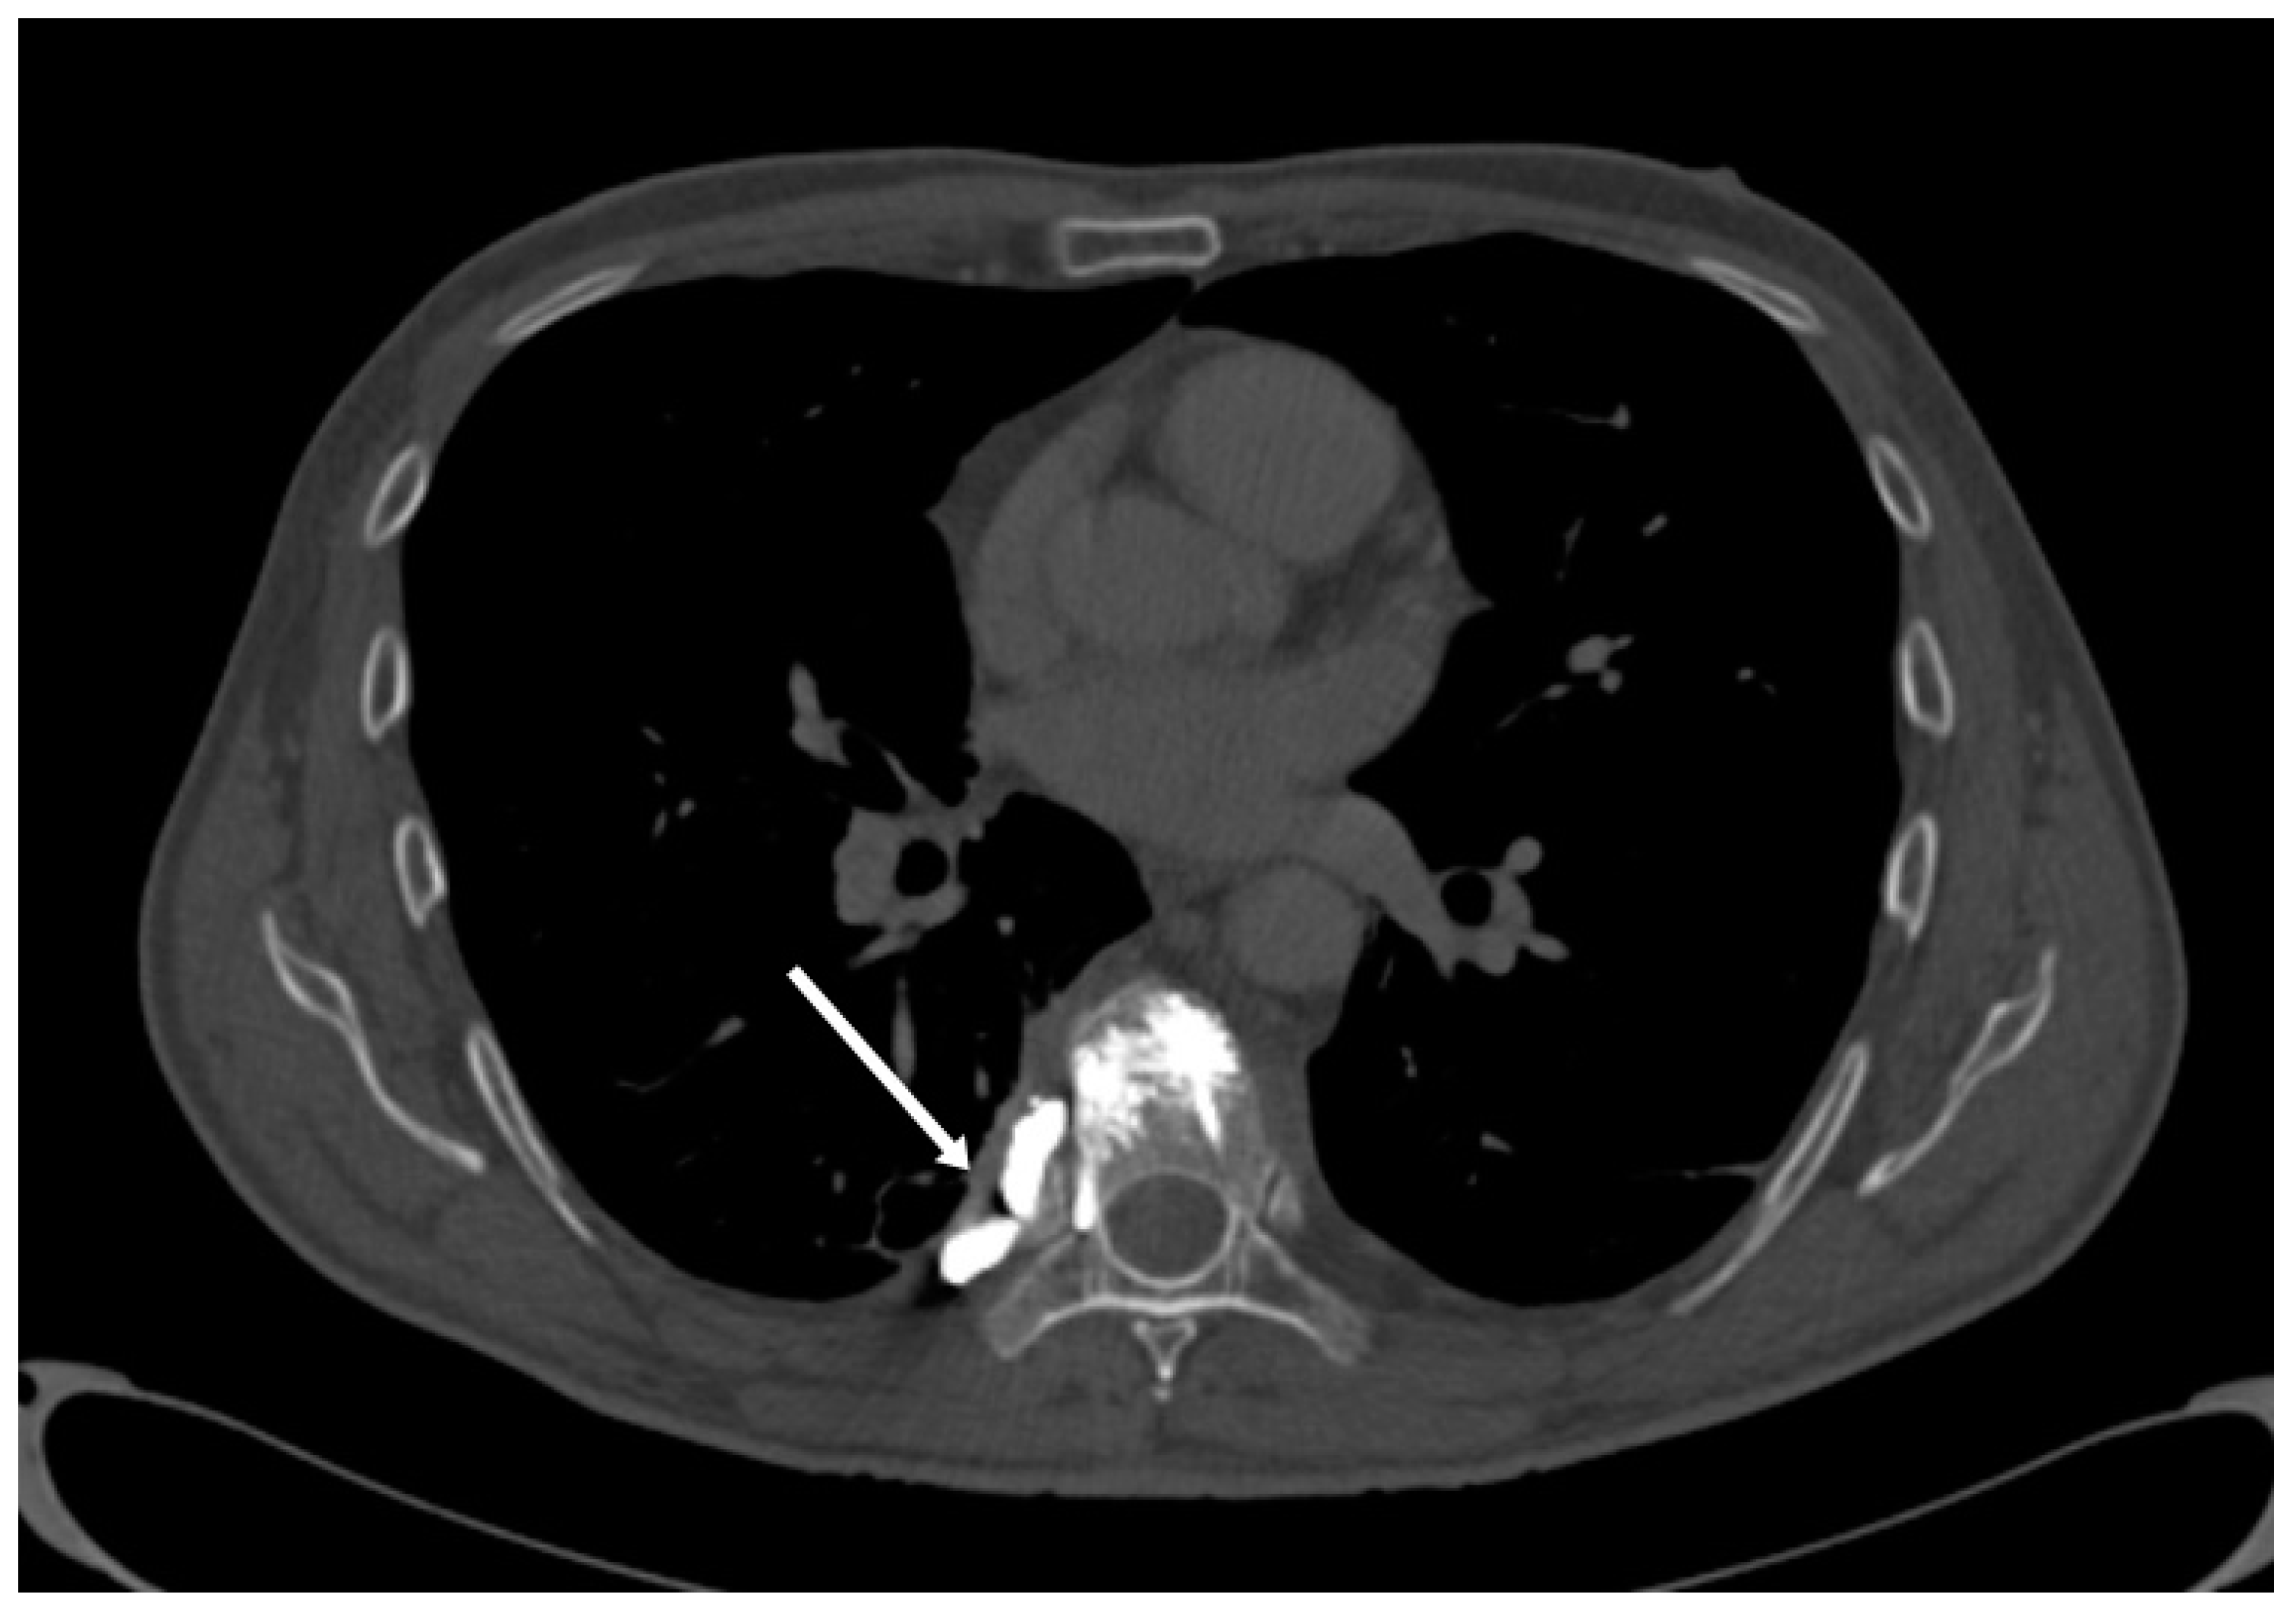

3.4. Venous System Cement Leakage and Pulmonary Embolism